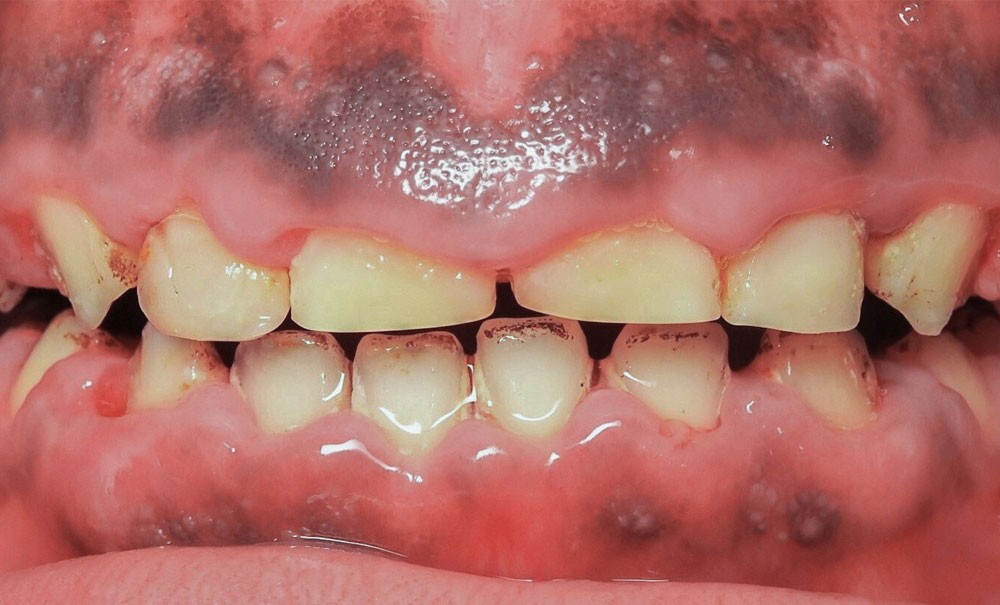

L’examen exobuccal met en évidence un profil dolichofacial et des anomalies majeures de structure dentaire (fig. 1). L’examen intrabuccal (fig. 2) montre :

- une hypoplasie sévère de l’émail ;

- une hyperplasie gingivale inflammatoire ;

- des hauteurs coronaires très réduites ;